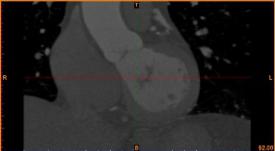

首先通过病人的心脏冠脉造影CT数据,获取病人的心脏冠脉三维模型。

病人的冠脉造影CT数据 提取出的冠脉三维数据